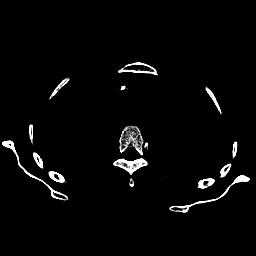

这里随机选取了两张张转换后的切片,分别选择不同窗宽的窗位,可以得到下图